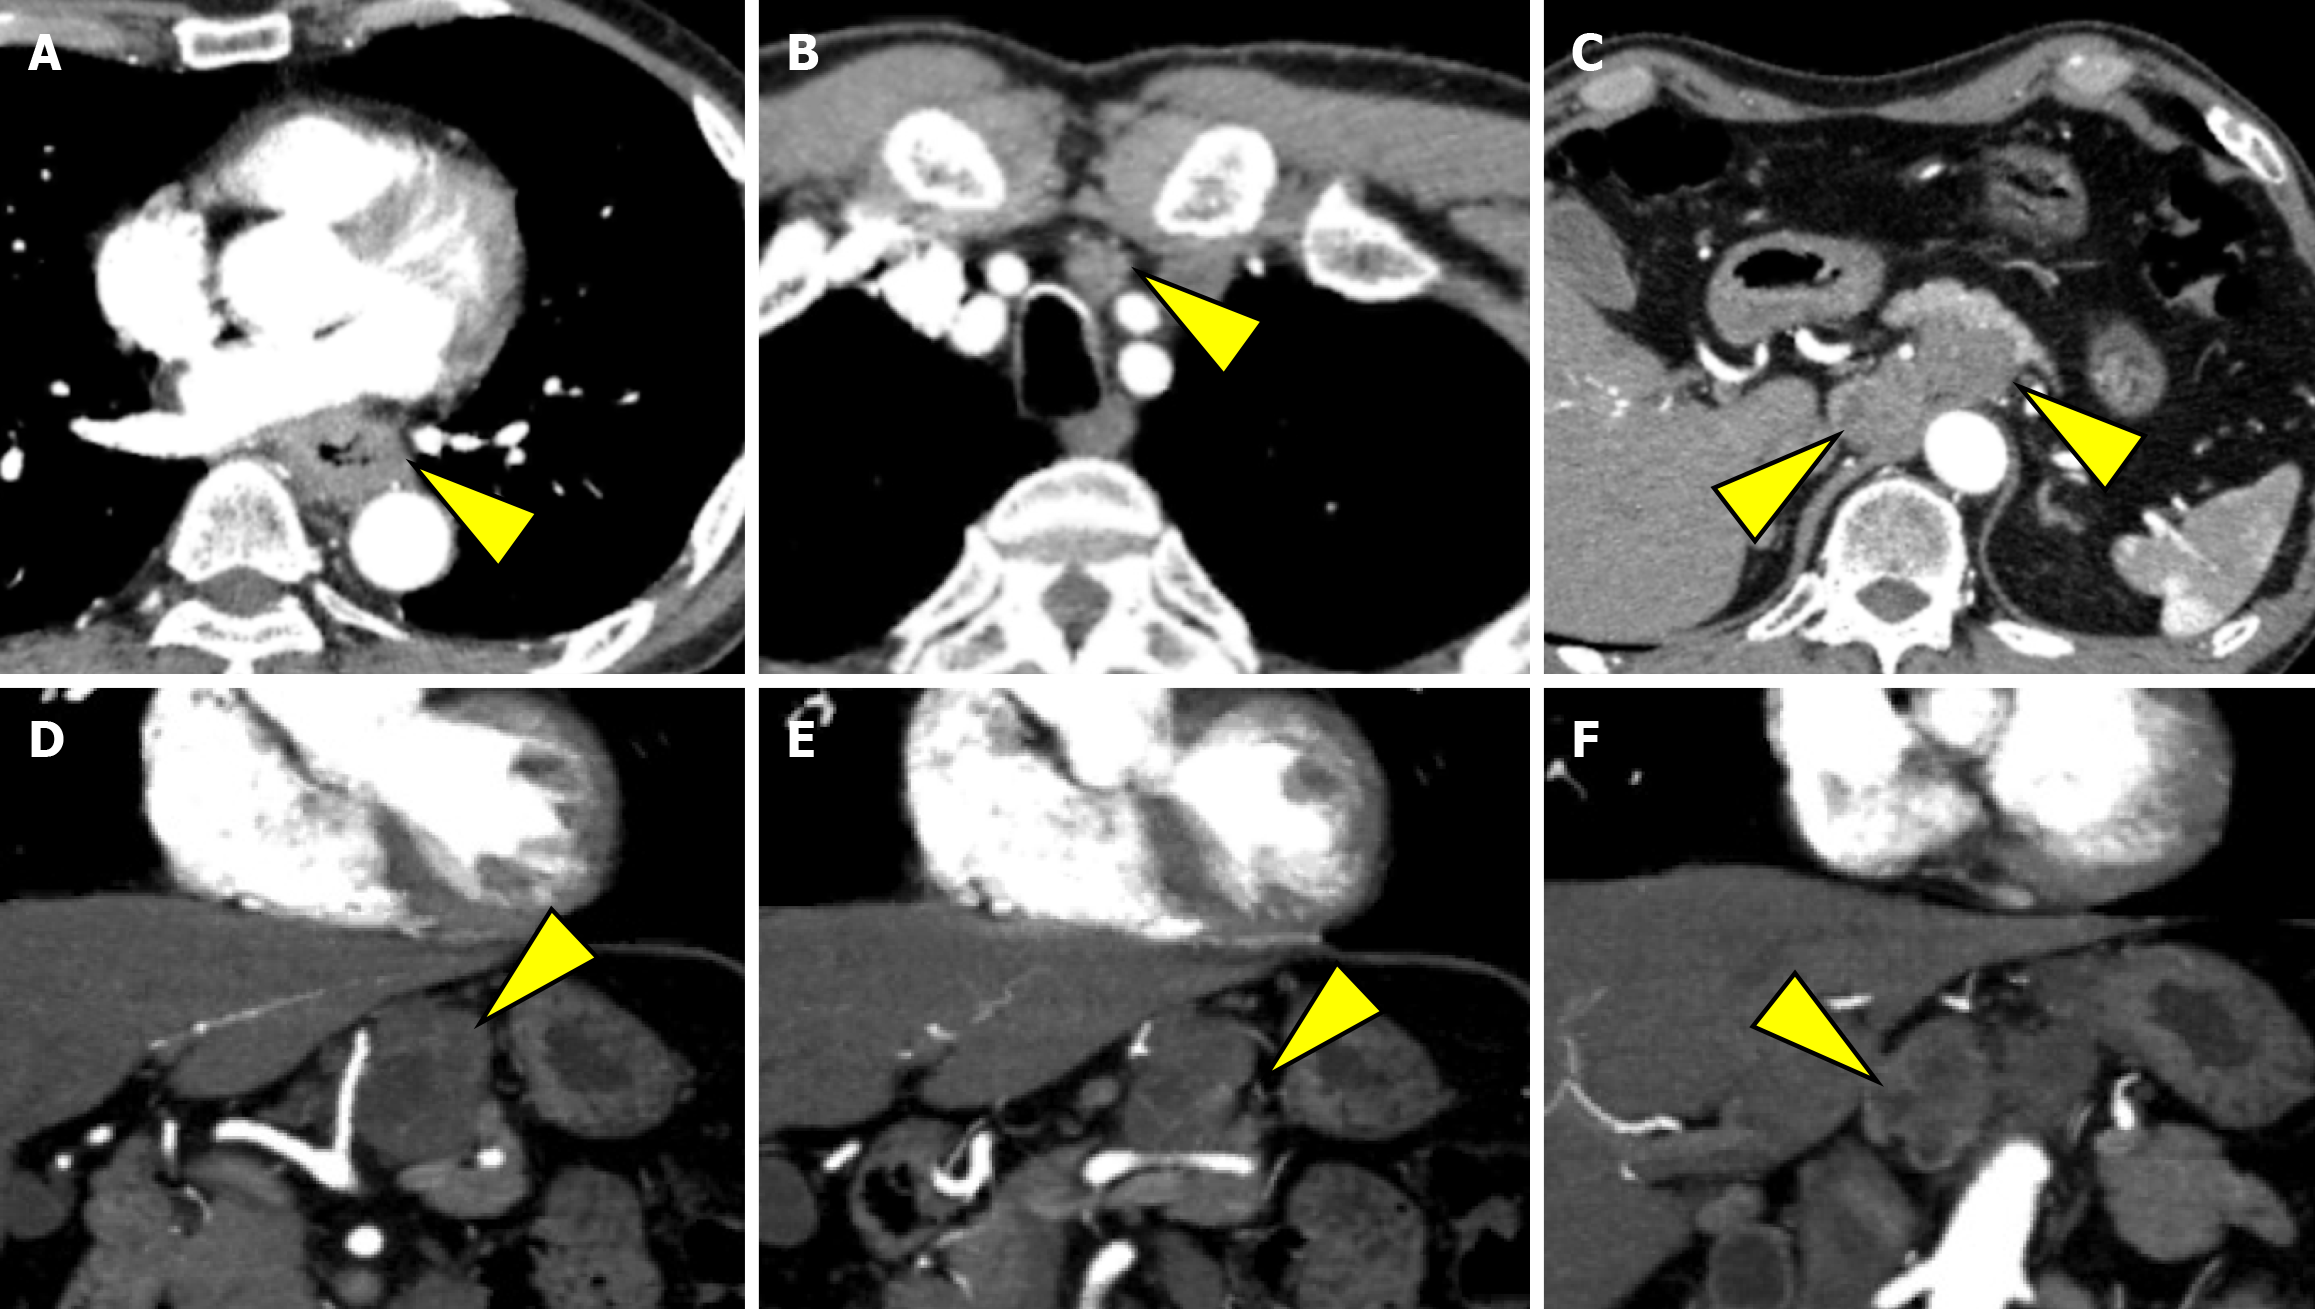

EGD revealed a semicircular, type 3 tumor in the middle thoracic esophagus, located 29-36 cm from the incisors (Figure 1A). Histopathological analysis of the biopsy specimen confirmed SCC. Computed tomography (CT) revealed irregular wall thickening from the middle to the lower thoracic esophagus, corresponding to the primary lesion (Figure 2A). In addition, an enlarged No. 101L lymph node measuring 15 mm was observed (Figure 2B), along with bulky suprapancreatic lymph node metastasis involving No. 8 and No. 9, forming a mass; furthermore, No. 11p was enlarged to 35 mm and showed direct invasion into the pancreatic body (Figure 2C-F). No other distant metastases were observed. On the basis of these results, the patient was diagnosed with locally advanced unresectable esophageal cancer of the middle thoracic esophagus [cT4a (No. 11p-pancreas) N4M0 cStage Iva][10,11].